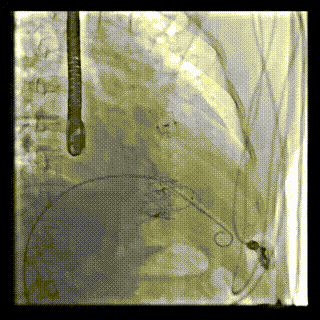

本周三例接受LuX-Valve Plus經(jīng)血管三尖瓣置換術(shù)的患者中,第一例患者為冠狀動(dòng)脈旁路移植術(shù)+Bentall+二尖瓣成形術(shù)后;第二例患者為永久起搏器植入術(shù)后,存在跨三尖瓣導(dǎo)線;第三例患者合并房顫、房缺及左心耳封堵術(shù)后。

三例患者入院后,葛均波院士團(tuán)隊(duì)周達(dá)新教授、潘文志教授、張?jiān)床┦?、陳莎莎博士及心超室的潘翠珍教授、李偉教?/strong>對(duì)患者的情況進(jìn)行詳細(xì)評(píng)估和討論,最終決定為三例患者選擇LuX-Valve Plus40mm、50mm和50mm型號(hào)的瓣膜進(jìn)行手術(shù)治療。手術(shù)后即刻拔除氣管插管,術(shù)后患者三尖瓣反流癥狀得到顯著改善,復(fù)查心超結(jié)果顯示人工三尖瓣瓣膜支架固定穩(wěn)定,瓣葉關(guān)閉形態(tài)未見(jiàn)異常,未見(jiàn)明顯反流。